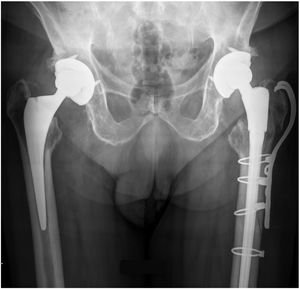

La artroplastia de cadera sigue siendo una de las cirugías más exitosas, con grandes resultados clínicos1,2. Dado el incremento de la esperanza de vida y las indicaciones de expansión en los pacientes más jóvenes, el número de pacientes activos con artroplastias de cadera está aumentando rápidamente3,4. Por tanto, las fracturas de cadera periprotésicas (PHF) (fig. 1) surgen como una carga5 para los servicios sanitarios y los pacientes, ya que suponen una morbilidad y mortalidad significativas6.

Materiales y métodosRealizamos un estudio retrospectivo de pacientes sometidos a artroplastia de revisión para el tratamiento de fracturas del vástago femoral periprotésico. Revisamos a todos los pacientes ingresados en nuestra Institución entre 2010 y 2020, con fracturas periprotésicas de tipo B2 y B3 de Vancouver, e incluimos a todos los pacientes tratados mediante artroplastia de revisión con vástago cónico estriado modular no cementado (fig. 2). Se excluyó a los pacientes con menos de un año de seguimiento, o sometidos a osteosíntesis. También se excluyó a los pacientes tratados con revisión acetabular simultánea. El estudio fue aprobado por el Comité de ética de nuestro centro. Al tratarse de un estudio retrospectivo se obtuvo la exención del consentimiento informado.